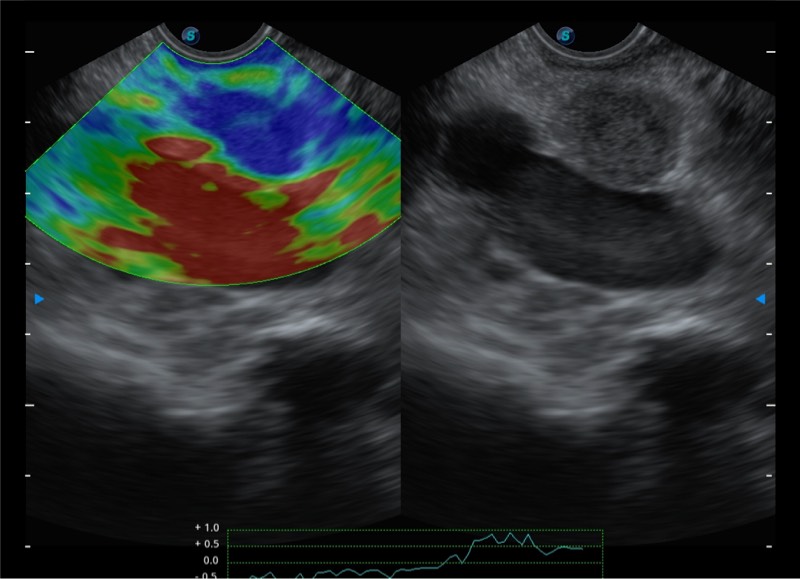

基于二十年的超声技术积累,公海贵宾会员检测中心提供了最新一代的独立超声主机,在提供高质量图像的同时满足多学科使用。具备常见多普勒技术并提供弹性成像、声学造影等高端影像技术。新一代传感器具有更强的抗干扰能力并减少图像伪影。

150°超声扫描角度

4-12MHZ宽频输出